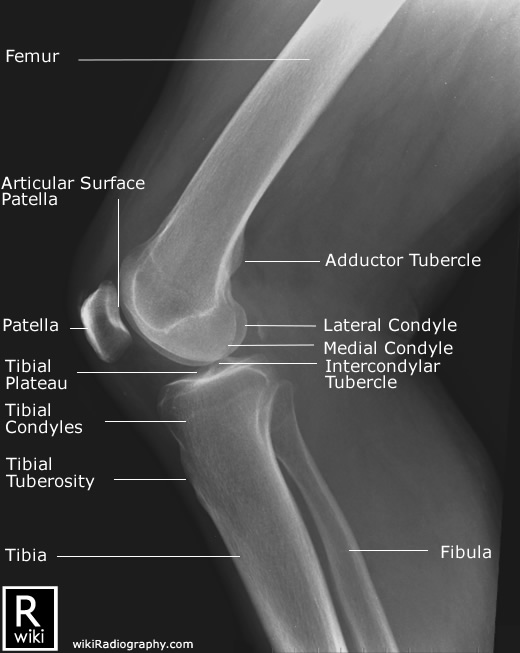

Spine Radiographic Anatomy

| AP view (Cervical) | AP view (Thoracic) |

![]() |

| AP view (Lumbar) | AP view (Sacrum) |

1) http://www.wikiradiography.net